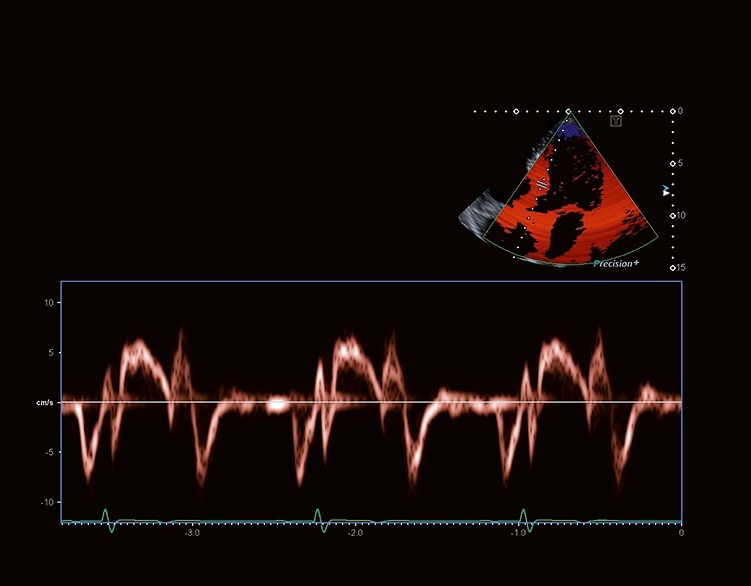

تکنولوژی پردازش سیگنال و پروب های با پهنای باند وسیع Aplio حساسیت، نفوذ و قدرت تفکیک مکانی فوق العاده را برای تمام حالات داپلر به ارمغان می آورد.

Aplio تصاویر Tissue Doppler و طیف های Pulsed Wave TDI با frame rate بالایی را به منظور زمان بندی دقیق فعالیت قلبی، به دو صورت بصری و کمّی، برای شما مهیا می‌کند.